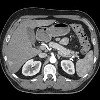

КТ брюшной полости

КТ брюшной полости. Диагностическое исследование позволяет получить послойную томографию высокого разрешения и разрешение внутренних органов, сосудов, лимфатических узлов, костных структур, мягких тканей брюшной полости. Компьютерная томография визуализирует все органы желудочно-кишечного тракта (желудок, поджелудочная железа, печень, желчный пузырь, селезенку, тонкий и толстый кишечник). Исследование является информативным для выявления различных патологий, в том числе воспалительных процессов, гнойно-деструктивных, опухолевых, дистрофических, травматических поражений органов брюшной полости и Это может быть выполнено путем изучения забрюшинного пространства (почки, надпочечники, мочевая система, лимфатические и кровеносные сосуды). Стоимость зависит от оборудования и использования контраста с внутривенным, пероральным или ректальным введением.